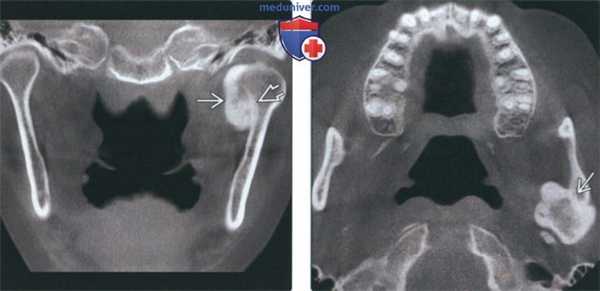

(Слева) На аксиальной КТ в костном окне на уровне сигмовидной вырезки справа визуализируется остеосаркома ветви и мыщелка нижней челюсти. Кортикальные пластинки утолщены, определяется лучистая периостальная реакция вокруг пораженных участков кости. Обратите внимание на асимметричный отек мягких тканей жевательного пространства и щеки справа.

(Справа) На аксиальной КТ с КУ у этого же пациента визуализируется опухоль, смещающая околоушную железу кзади и кнаружи, и вероятно, прорастающая в нее. Опухоль распространяется в правую верхнечелюстную пазуху.